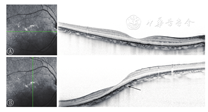

(1)单纯DSM12只眼,占35.3% (12/34)。屈光度在-900~-2 000 D之间,眼底近视改变,OCT可见黄斑区脉络膜下的向内隆起(图1B),不同于一般病理性近视眼黄斑区向外凹陷的表现(图1A),不合并其他眼底病变。

注:A为一般病理性近视眼:OCT表现为黄斑区向外凹陷。B为64岁女性(左眼,屈光度为-1200D):OCT图像可见黄斑区脉络膜下圆拱形向内隆起

注:A:横向OCT扫描可见垂直方向无明显的黄斑部脉络膜下的隆起;B:纵向OCT扫描可见横向黄斑部脉络膜下有轻微隆起。

参照Curtin[10]提出的葡萄膜肿的10种类型可知,DSM不属于其中的任一类型,而是在OCT上观察到的一种新的病理形态,在国内尚未见有相关的论述报告。Gaucher等[11]首次通过OCT发现了DSM,目前DSM在高度近视眼中的发生率为20%(225/1118)[12]。随后,Caillaux等[5]通过SD-OCT对DSM进行水平向与垂直向的双向扫描,并将其形态学特点归纳为3个类型:①圆顶的拱形,发生率为20.8%(10/48)。②横向椭圆形的拱形,发生率为65.2%(30/48)。③垂直向椭圆形,发生率为16.7%(8/48)。临床上,后两种并不表现为典型的拱形凸起,在OCT图像中易被漏诊,与扫描方向有关。也有报道表明由于后葡萄膜的不对称扩张,可能导致横向椭圆形向拱形转变[2]。